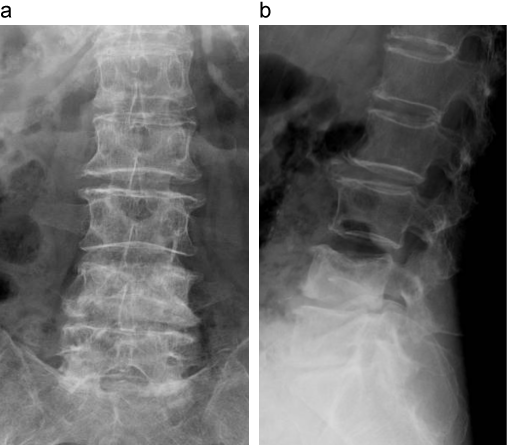

症例1のX線画像

第4腰椎に椎体骨折を認める。

a:X線正面像

b:X線側面像

出典

img

1: 著者提供